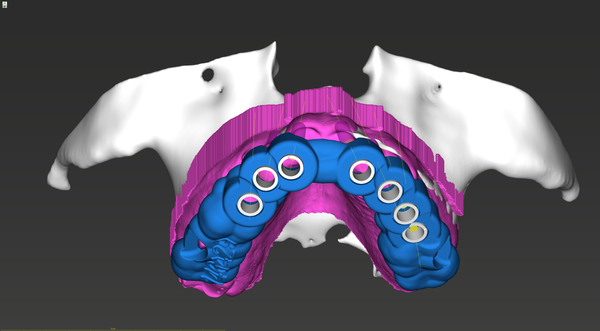

- Ability to import CT/CBCT Scan in Multi-DICOM format.

- STL Registrations.

- Treatment planning, Panoramic curve, view, and nerve tracing.

- Design and place sleeves.

- Design surgical guides.